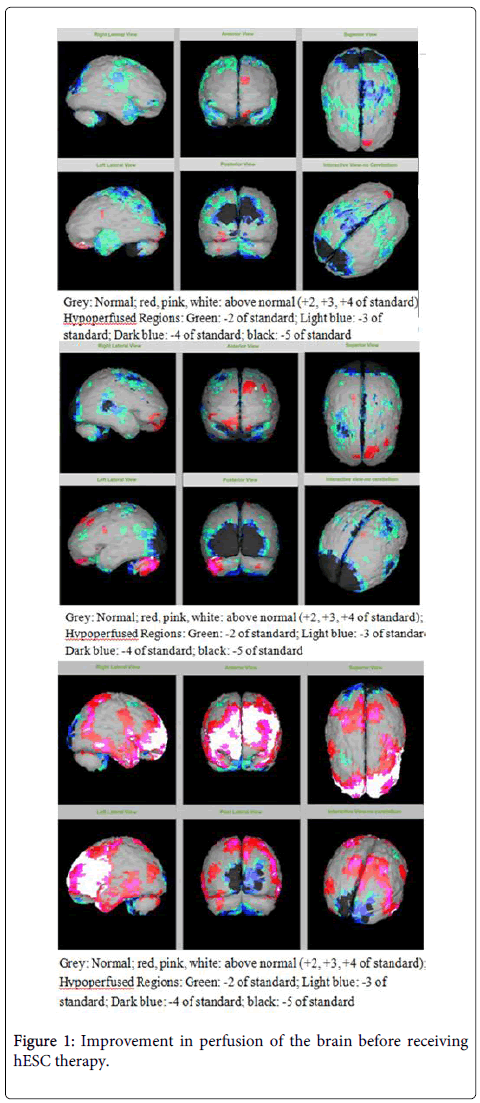

圖2:接受hESC治療后大腦灌注得到改善

該患者的SPECT掃描如圖1和2所示。

SPECT掃描

在研究開(kāi)始和結束時(shí),23名患者接受了SPECT掃描。在枕葉或額葉或雙葉中觀(guān)察到灌注不足。23例接受SPECT掃描的患者中,5例患者表現為枕葉灌注不足,7例患者表現為額葉灌注不足,11例患者表現為枕葉和額葉灌注不足。

總體而言,治療結束時(shí),2名患者的灌注正常,18名患者(12名男性和6名女性患者)顯示灌注顯著(zhù)改善(>60%),3名患者顯示灌注中度改善(30-60%)。大多數在接受hESC治療前額葉和枕葉嚴重低灌注的患者在接受 hESC 治療后情況有所改善。23名可獲得SPECT掃描報告的患者的GMFCS評分在hESC治療后有所改善(表2)。

眾所周知,神經(jīng)干細胞可以通過(guò)重新填充受損區域并防止細胞進(jìn)一步退化來(lái)恢復正常視力。hESC通過(guò)增殖成相似的細胞類(lèi)型來(lái)啟動(dòng)受損細胞的再生。在本研究中觀(guān)察到灌注改善,這反映在SPECT掃描中。詹森等人研究顯示,一名5歲腦癱患者在接受臍帶血干細胞治療2個(gè)月后視力有所改善。